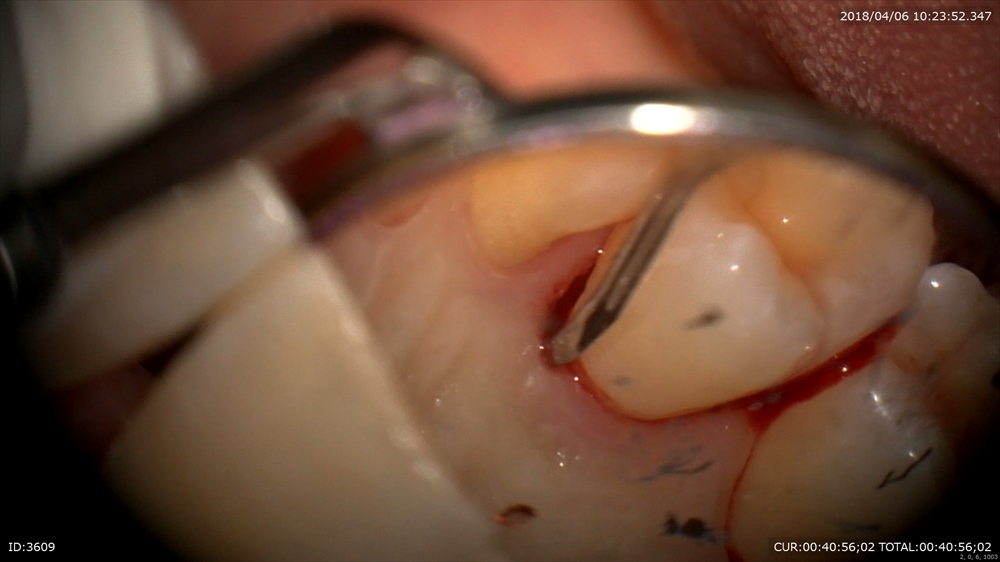

ここに6mmのポケット

ある道具を用いると内部が膨らみ

見えます。

みえたら16倍の倍率で歯石をとります。シャープニングも大切。

ここは右上7番のポケット内部。。見にくいですが。マイクロスコープで

歯石発見

歯石だけをとる